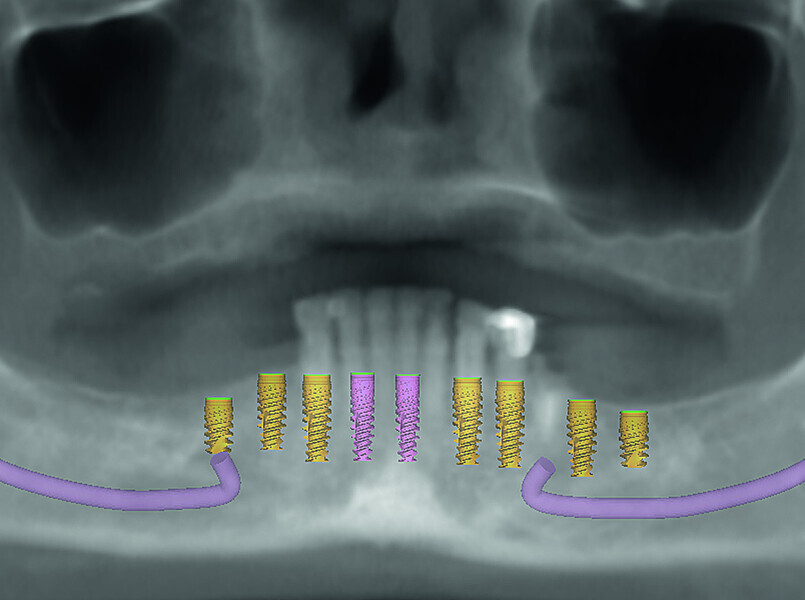

Fig. 6: Dentofacial analysis of proposed implants in mandibular arch.